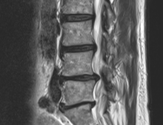

触覚検査 右L4、L5領域やや知覚鈍麻

右前脛骨筋やや弱化

L4/L5/S1間の右椎間関節に圧痛と放散痛

両仙腸関節機能低下、